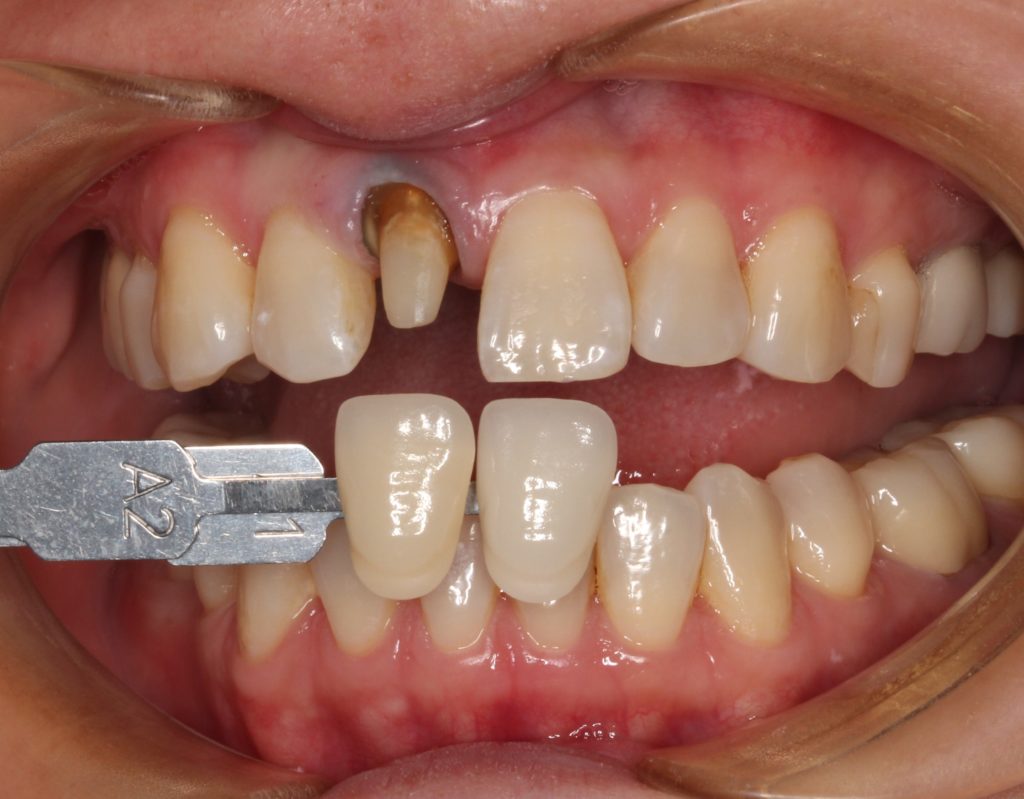

40代女性。「差し歯の入っている歯の根元が黒く、綺麗に治したい」という希望の方です。

早速、お口の中を見てみましょう。

矢印の歯ですが、根元が黒いのがすぐに分かります。

こちらの歯は若い頃に差し歯になってしまったようで。年々、根元のが目立ってきたようです。

歯の色見本を合わせ、周囲の歯の色を確認、記録します。

専門の歯科技工士が人工歯を製作し、後日完成した歯を装着します。